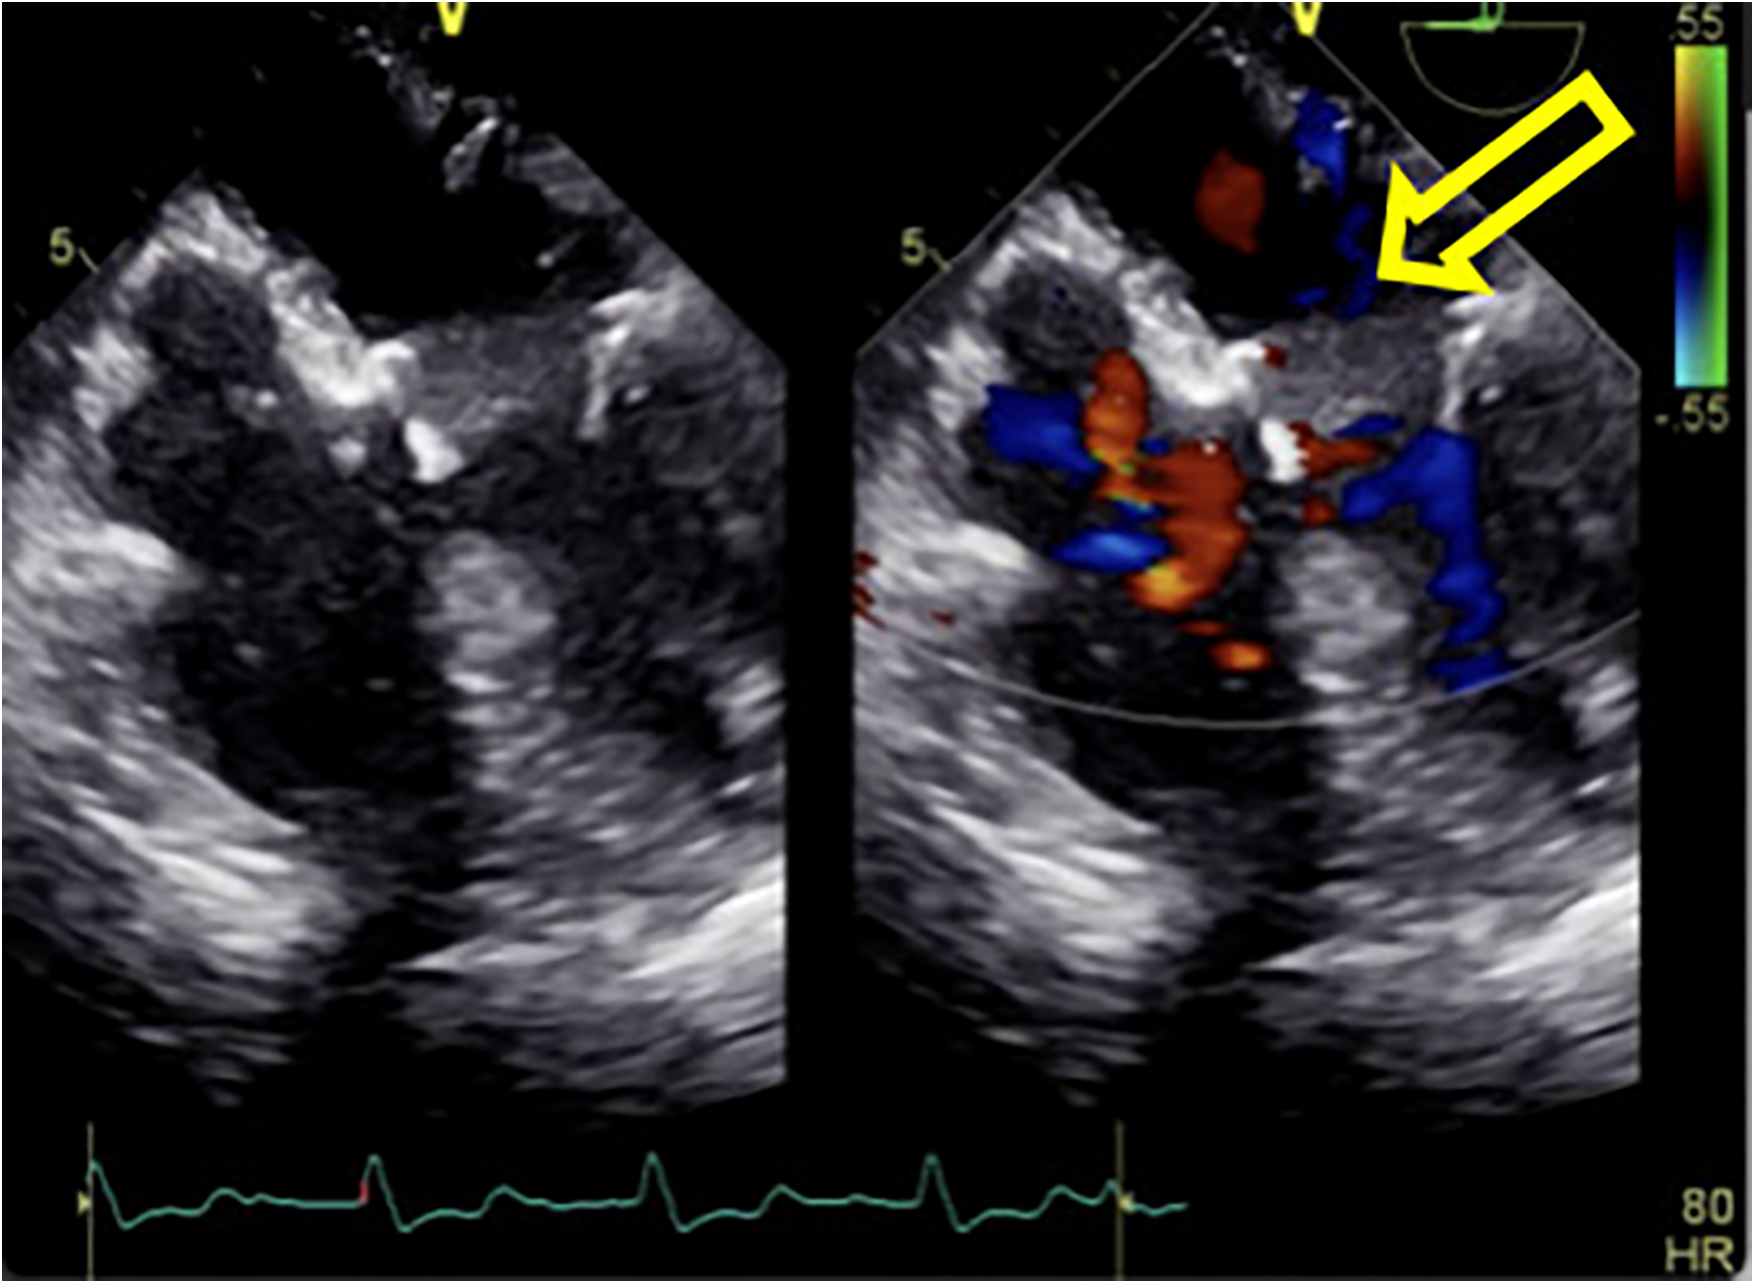

Given this emergent situation, cardiopulmonary bypass was reinitiated to resolve the circulation crisis. The results of TEE monitoring showed that the left atrial dissection hematoma was compressing the left ventricular inflow tract, which accelerated blood flow through the mitral valve, causing mitral valve relative stenosis. In addition, TEE found pulsatile blood flow in the hematoma at the left atrioventricular groove on the posterior wall of the left atrium after the second cardiopulmonary bypass (Figure 2), suggesting that this blood flow was related to the left coronary circumflex branch. However, the relationship between the left circumflex branch and the dissection could not be determined. Because the criminal's blood flow (blood vessels) was located in the posterior atrioventricular groove and could not be explored through a surgical incision, we ultimately decided to incise the left atrial endocardium to drain the decompression hematoma through the left atrium (Figures 3, 4). The specific method applied was to reopen the right atrium and atrial septum along the original surgical incision. After confirming the correct position of the artificial valve and the integrity of the left atrial endocardium, the latter was incised for drainage and decompression, and the atrial septum and right atrium were resutured. The patient was admitted to the ICU for further management and discharged home after 16 days.

Figure 3. The yellow arrow indicates the site of incision and drainage. (A) Surgical treatment method: After confirming the integrity of the left atrial endocardium and the correct position of the artificial valve, the left atrial endocardium was incised for decompression and drainage. (B) TEE 3D reconstruction detected the drainage port of the left atrial endocardium incision for decompression.

Figure 4. The hematoma on the posterior wall of the left atrium significantly decreased in size after incision of the left atrial endocardium for decompression and drainage.